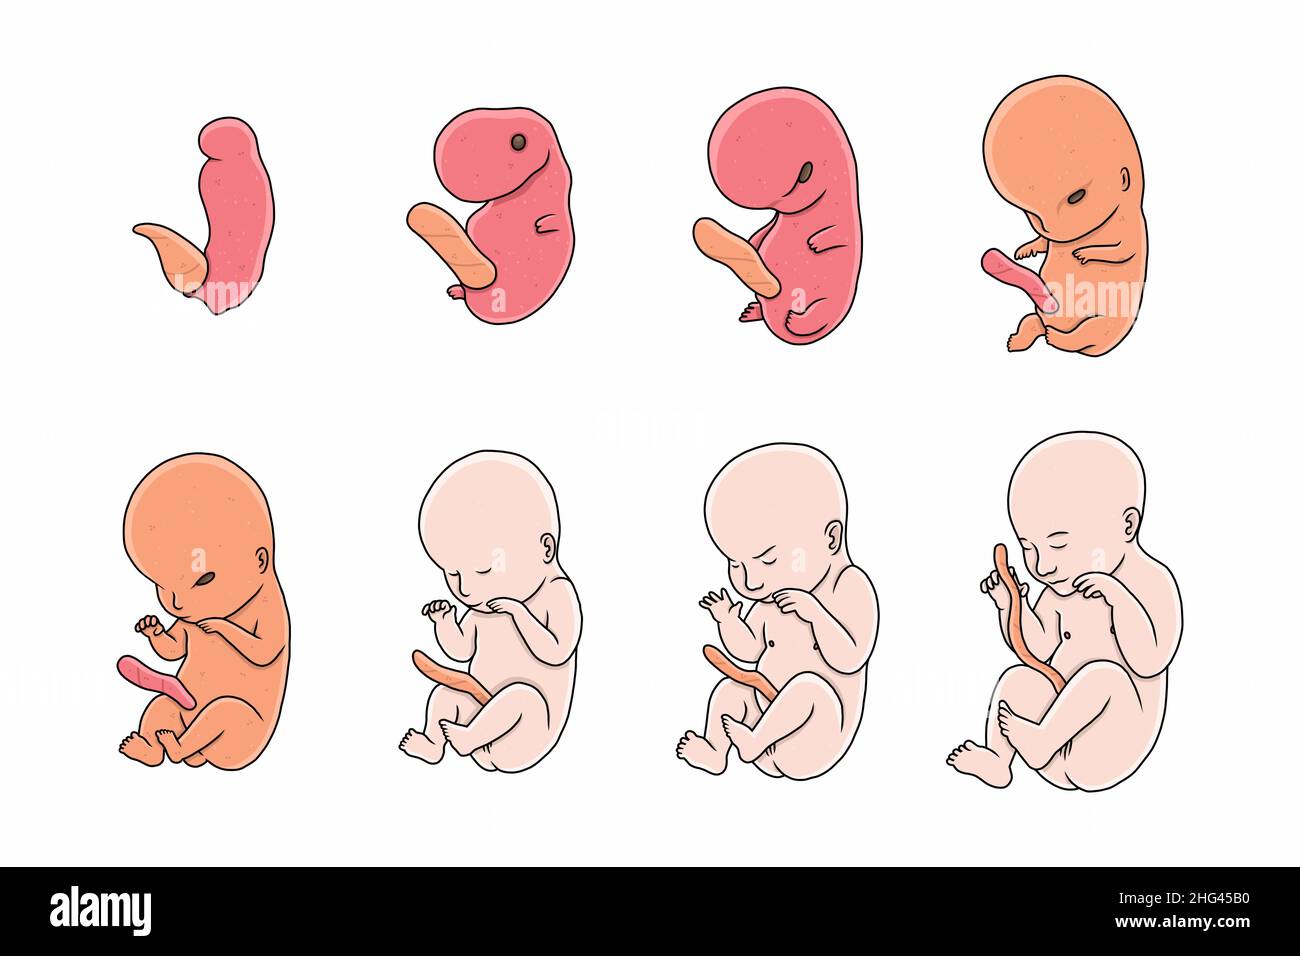

In addition to the information above, here is a curated collection of images related to Fetal Movements Hi Res Stock Photography And Images Alamy.

- 401 Fetal Movement Images, Stock Photos & Vectors | Shutterstock

- 8,500+ Fetal Baby Stock Photos, Pictures & Royalty-Free Images - IStock